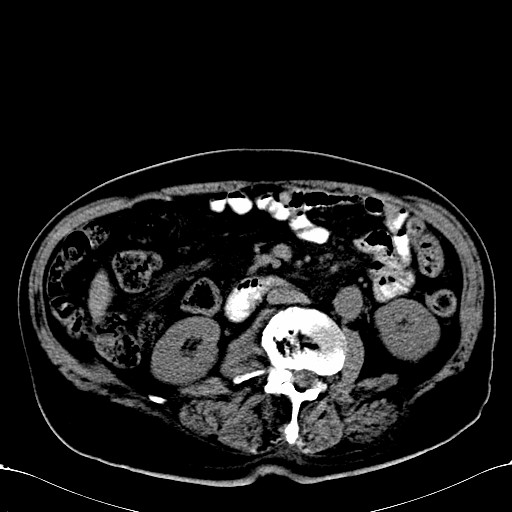

标题: CT28270:胰管扩张,肝多发占位

患者,男,75岁。

肝脏多方低密度结节,边缘模糊,考虑多发转移,胰管明显扩张,建议增强扫描钩突情况

肝脏多发低密度灶,胰头似呈低密度,胰管扩张,建议增强,

胰管显著扩张,但胆总管未见扩张征象,不太符合胰头占位!考虑慢性胰腺炎.胃窦占位并肝内转移可能!mrcp胃镜增强一起上!